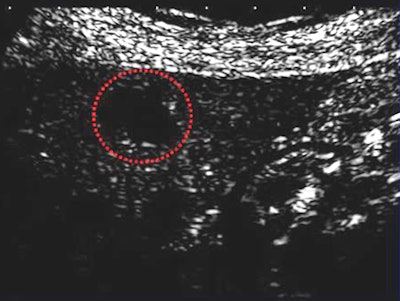

![]() |

| CAD correctly classifies a well-differentiated HCC in an MFI image acquired using the Sonozoid contrast agent. All images courtesy of Junji Shiraishi, Ph.D. |